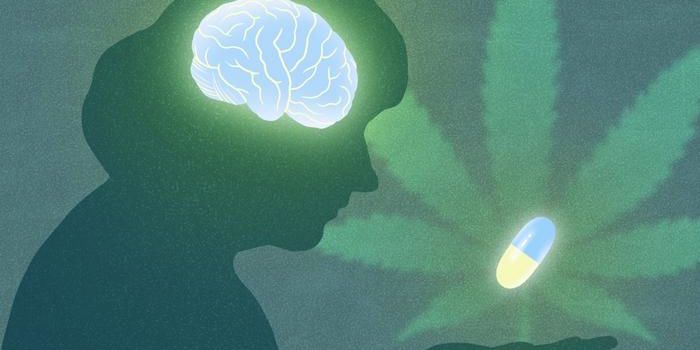

FEB 13, 2025Cannabis SciencesThe proportion of new schizophrenia cases linked to cannabis use in Ontario, Canada, increased from 4% prior to legaliza ...

FEB 05, 2025Cannabis SciencesA recent study published in the Journal of the American Medical Association has provided valuable insights into the effe ...

JAN 30, 2025Cannabis SciencesBoth long and short-term cannabis use is linked to less brain activation and worse performance during working memory tas ...